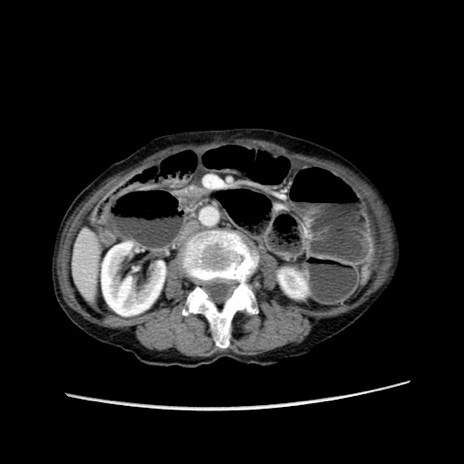

症例25(横断像)

【症例】80歳代女性

【主訴】胸のつかえ感

【現病歴】約9時間前に食後から胸のつかえた感じあり、嘔吐あり、来院。

【既往歴】胃癌(全摘)、胆摘、虫垂炎

【身体所見】心窩部に圧痛あり、反跳痛なし。

【データ】WBC 5700、CRP 0.05